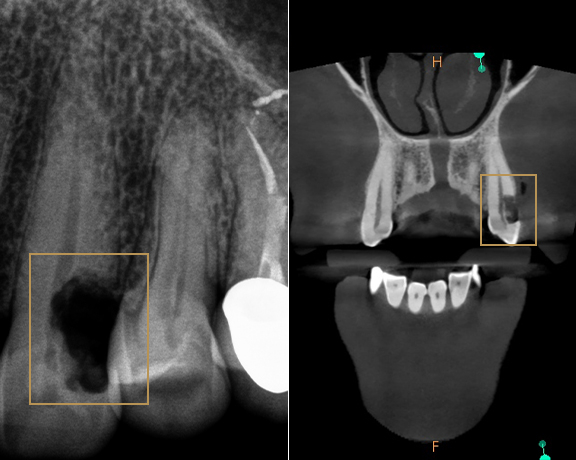

W badaniu wewnatrzustnym przeprowadzonym standardowo (lusterko i zgłębnik) zobrazowanym dodatkowo dla pacjenta obrazem z kamery wewnątrzustnej widoczna jest wyraźna szczelina pęknięcia w obrębie guzka podniebiennego. Pani doktor badanie uzupełniła tomografią komputerową. Obraz CBCT zęba potwierdził  rozpoznanie, pokazując jak głęboko sięga szczelina złamania. Warto w tym miejscu zwrócić uwagę, że nie wszystkie projekcje radiologiczne pokazują faktyczną sytuację zęba. W tym przypadku, w standardowym rzucie - brak widocznych zmian. Dlatego często tomografia komputerowa 3D pozwala nam realnie ocenić problem, a także zaplanować odpowiednie leczenie.

Na podstawie badania dr Pakosz - leczenie kanałowe w poprzednim gabinecie przeprowadzono prawidłowo. Niestety odbudowa zęba nie została wykonana w zalecany sposób. Nie wykonano odbudowy protetycznej zęba, nie zacementowano również wkładów w kanałach. Ich działanie protekcyjne jest mocno dyskutowane. W sytuacji jednak, gdy mamy rozległą, długa komorę zęba i szerokie wejście do niej, z pewnością może być to czynnik chroniący przed głębokim, poddziąsłowym złamaniem. Trzeba pamiętać, że to przedtrzonowce są najczęściej łamiącymi się zębami po leczeniu kanałowym. Sytuację u pacjenta komplikuje brak zęba 15 oraz mocny poziomy wzorzec żucia.